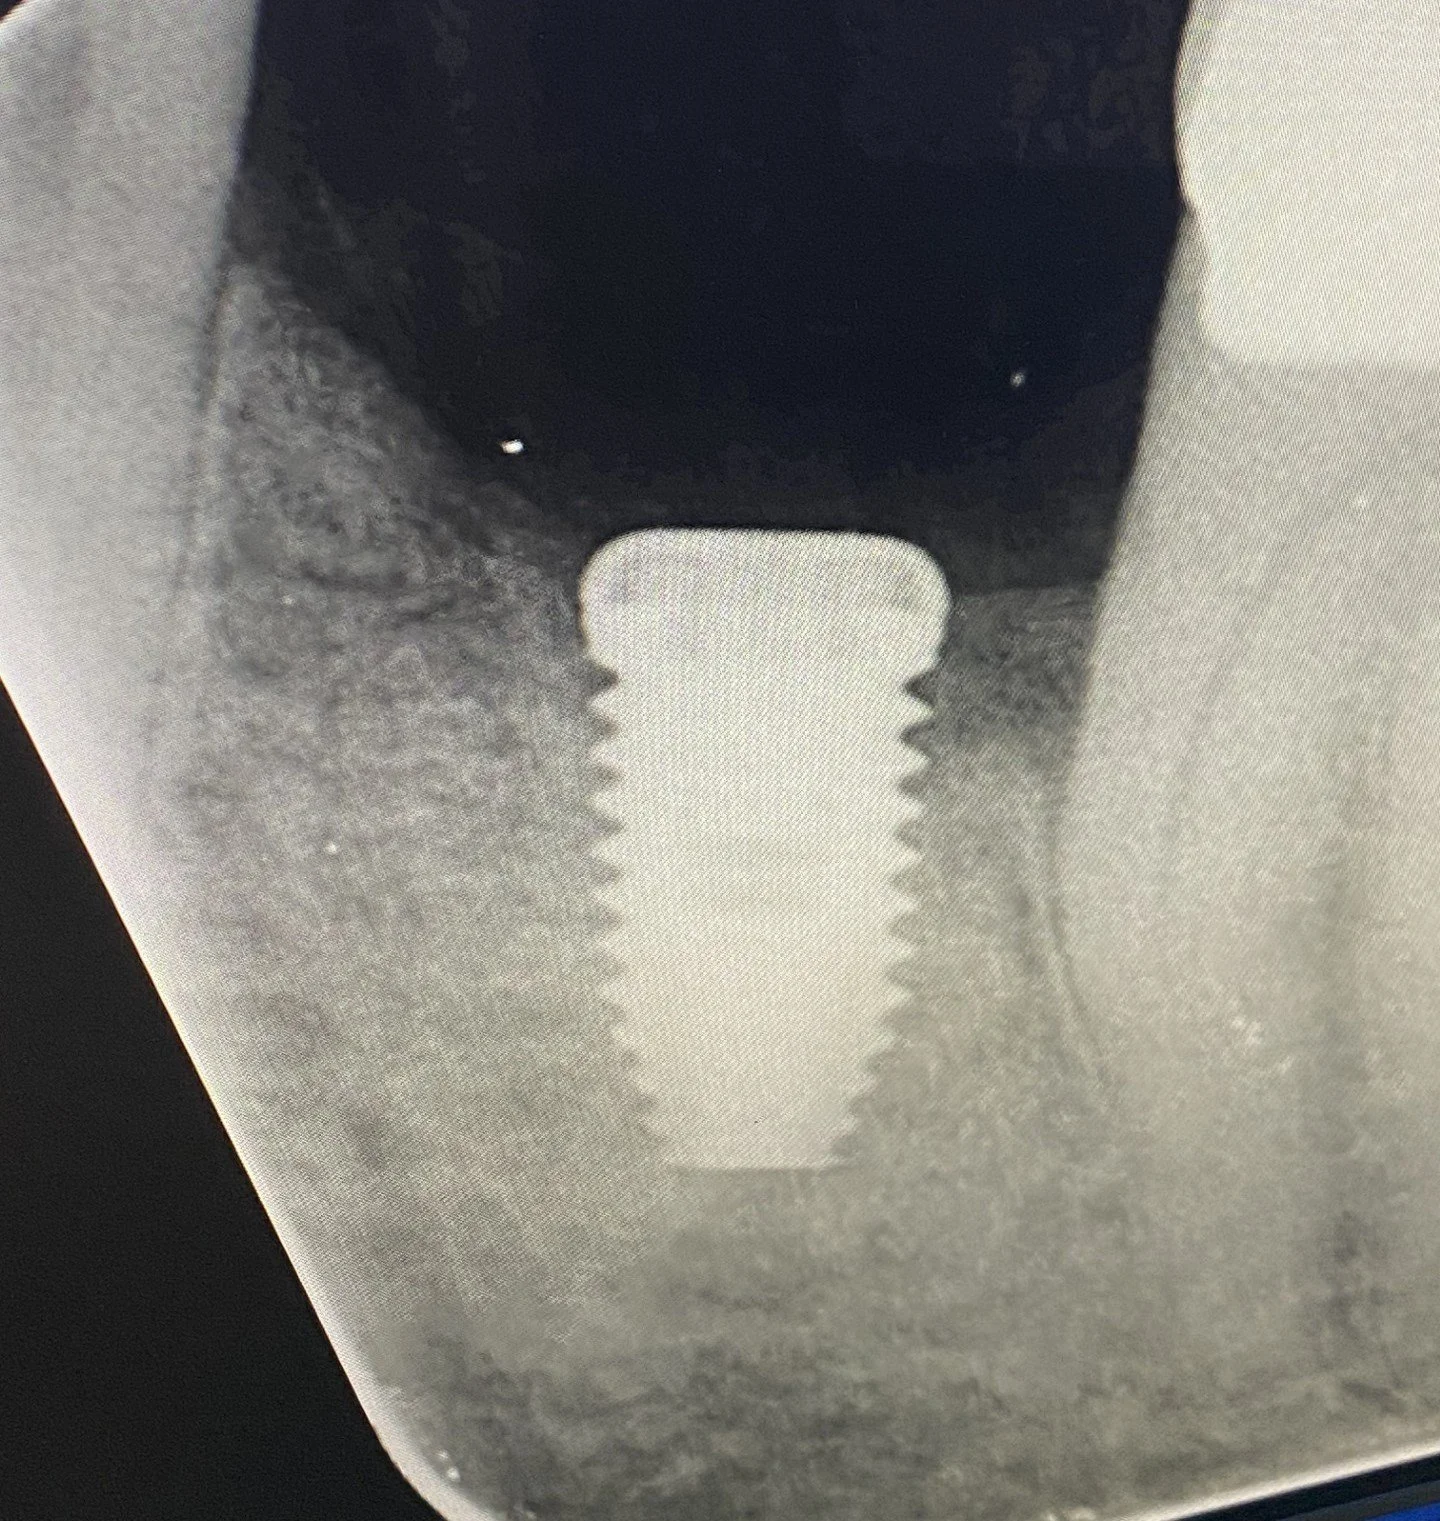

THIS IS A CT SCAN OF A PATIENT’S LOWER JAW IN THE 36 MOLAR REGION FOR TREATMENT PLANNING AND SELECTING THE APPROPRIATE LENGTH AND DIAMETER IMPLANT FIXTURE. THIS SLICE REPRESETS THE CHOSEN CENTROID POSITION FOR THE FUTURE IMPLANT FIXTURE WHICH WAS 10 MM LONG BY 5 MM IN DIAMETER. COLOURED LINE DIAGRAMS WERE USED TO FIND AN APPROPRIATE POSITION AND ANGULATION FOR THIS IMPLANT FIXTURE TO AVOID ENDANGERING THE MANDIBULAR NERVE AND OTHER STRUCTURES.

THIS RADIOGRAPH ILLUSTRATES THE WIDE PLATFORM 10 MM LONG BRANEMARK FIXTURE CENTRALLY PLACED BETWEEN THE TWO TEETH. A RADIOLUCENCY OR GREY/BLACK CIRCLE IS EVIDENT 2 MM BELOW THE END OF THE FIXTURE WHICH IS THE MANDIBULAR NERVE CANAL. THE TOP OF THE FIXTURE HAS BEEN SEALED WITH A COVER SCREW AND THE GUM LINE SUTURED.